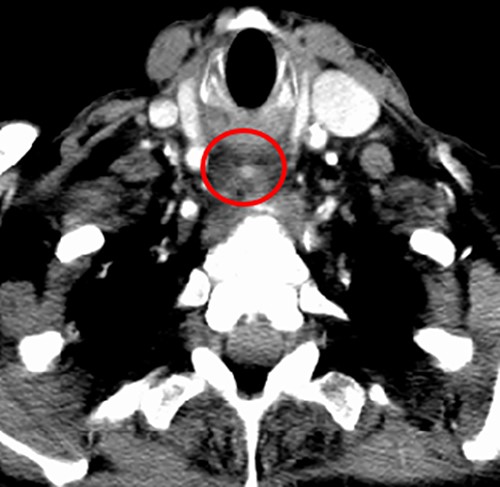

Computed tomography (CT) was performed showing a large, ill-defined mass of which the exact aetiology was initially unclear but suspicious for a primary hypopharyngeal malignancy. Of note, within this mass, a small air collection was observed, containing a 3-mm hyperdense focus (Fig. 2).

CT neck; post-cricoid mass containing an air locule with a 3-mm hyperdense mass (red circle) in the caudal end of this.

There are notable differences between our case and others previously reported. Although acute oesophageal obstruction in ZD has been previously described, it appears to occur exclusively in the presence of large diverticula (>4 cm) which are often impacted with food. Our patient had a small 1.1-cm ZD without food impaction. Identifying the presence of food bolus impaction is critical in these patients due to an increased risk of major complications, such as oesophageal ischemia, perforation or mediastinitis, if the impaction is not addressed within 24 hours of onset [1]. Our patient was previously asymptomatic and had no antecedent symptoms which is in contrast to other published cases. In the present case, it appeared that oesophageal obstruction was caused by localized oedema of the diverticulum triggered by the impaction of an ibuprofen tablet into this, which correlates with the small hyperdense area at the centre of the phlegmon observed on CT (Fig. 2). This is supported by the patient’s history, laryngoscopy findings, imaging and rapid response to intravenous steroids. Due to this, ZD may be an appropriate term. Oral medications, especially ibuprofen, causing oesophageal oedema and obstruction have been described, however, this is usually caused by the large tablet size [10].